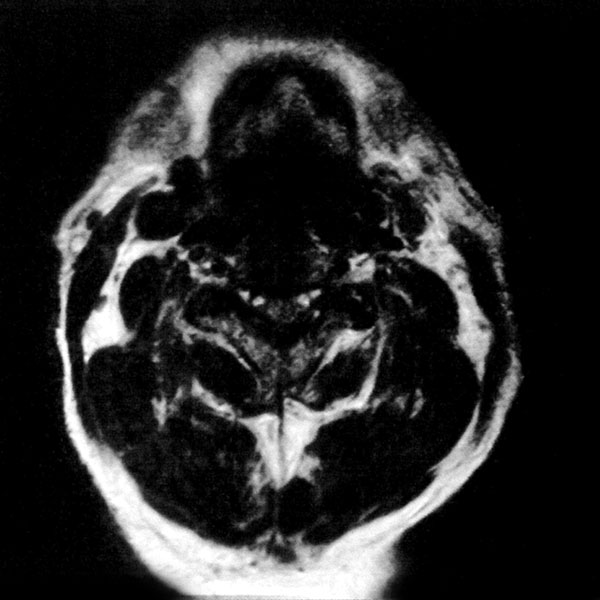

MRI検査

2025年9月16日スタート!!1.5T MRI SIGNA Creator(GE社製)

新しいMRI装置では従来の装置と比較し、高画質、かつ短時間での検査が可能となります。

- AI 機能を搭載:従来の装置と比べかなりの高画質が期待できます

- 従来の装置では難しかった微細な変化の描出にも期待がもてます

- PROPEELR 機能により、動きを抑えたきれいな画像が得られます